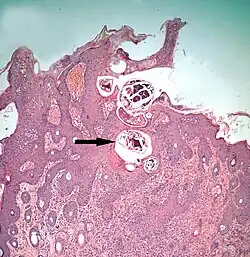

The diagram Mite infestation sites on skin shows where typical infestations of different taxonomic groups mites on livestock animals occur on or in the host's skin.[9] The position of these mites in relation to the skin or other organs is crucial for their feeding and also for their veterinary diagnosis and options for treatment. The mites either feed on the tissues of the skin using penetrating mouthparts or on the inflammatory exudate that results from the action of the mouthparts and saliva of the mites on the skin.[12] Demodectic mites have mouthparts adapted to penetrate and suck out the contents of individual cells of hair follicles.[13] It is usual for all active stages of the mite lifecycle to feed as parasites, but the trombiculid mites are an exception. Most of the parasitic mites do not feed directly on blood, but the dermanyssid mites and larval trombiculid mites directly suck up capillary blood as their exclusive food. The tube through which food is ingested and saliva excreted during feeding is formed in most mites by apposing the sheath that contains the chelicerae against the hypostome. However, the trombiculids are an exception. Some species of mites (Analgidae) have adapted to feeding on keratin and skin debris amongst the feathers of birds, and other species have adapted to feed directly on internal tissues such as air-sacs or lungs (Cytoditidae and Laminosioptidae). Psoroptic mites feed superficially at the stratum corneum; the photograph of a histological section of skin infested with Psoroptes ovis, and the photograph of the surface of a host's skin infested with P. ovis looking like white dots, show this type of feeding. Sarcoptic mites feed by burrowing within the living layers of the epidermis, mainly stratum spinosum. Demodectic mites feed in a position technically external to the skin, between the epidermis and the hair shaft in hair follicles. Dermanyssid and trombiculid mites feed whilst external to the skin by piercing the skin with, respectively, their chelicerae or a stylostome feeding tube. Mites at other sites feed by using their chelicerae to scrape either at the skin surface, or at base of feather, or to penetrate and scrape at internal tissue such as air-sac or lung.

Psoroptic skin disease

The clinical manifestation of infestation with psoroptic mites is usually called mange and sometimes scabies, but the skin disease of sheep caused by Psoroptes ovis is often known locally as sheep scab. This species may affect its hosts severely enough to reduce their gain in weight.[25] Costs to farmers of controlling sheep-scab in Britain were at £8 million (US$12 million) annually in 2005.[26] Transmission between hosts is readily accomplished by contagion during flocking contact and also on fomites such as scraps of sheep's wool because these relatively large and robust mites can survive for one to two weeks off their host. Psoroptes ovis infests the superficial layers of the skin. Irritation of the outer skin by the mite's mouthparts and saliva results in a complex form of cutaneous hypersensitivity and inflammatory exudation of serum and fresh cells. The mites feed on this moist exudate.[27] The skin loses its hair (depilation) at the sites of infestation and this may be extensive. As a result of the movement of the mites into areas of fresh skin, large scabs accumulate on the raw skin left behind. The mites cause intense pruritus (itching). In cases of heavy infestations, the host grooms compulsively, aggravating the depilation, and it may become mentally distressed.[28] Psoroptes ovis infests sheep worldwide and can be a serious welfare and animal-production problem for sheep farmers. Infestations of cattle with mites of the similar genus Chorioptes, in combination with Sarcoptes mite infestation, has been shown to cause a failure to gain body weight by 15.5 to 37.2 kilograms (34+1⁄8 to 82 lb) over a two-month period compared to cattle without the mites.[29]